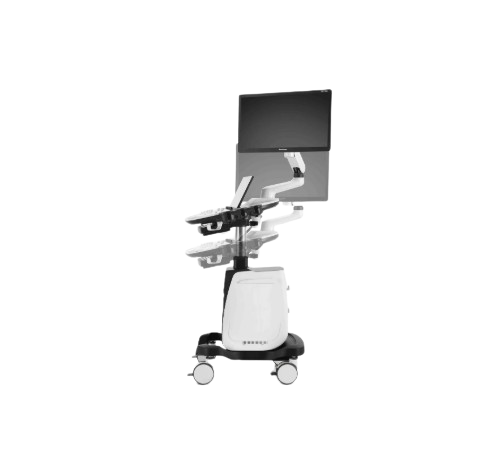

SonoScape P12 Elite Ultrasound Machine

The SonoScape P12 Elite Ultrasound machine is a high-performance diagnostic imaging system designed for hospitals and clinics in Bangladesh. Featuring advanced imaging technology, superior Doppler performance, and user-friendly operation, it delivers accurate results with Quick workflow. Available at the Best price in Bangladesh with Special discount and Low Price offer from trusted medical equipment suppliers in Bangladesh.

- System Type: Trolley Ultrasound Machine

The SonoScape P12 Elite Ultrasound Machine is designed to meet these modern healthcare demands. Developed by SonoScape, a globally recognized medical imaging manufacturer, this system combines advanced imaging technology, intelligent workflow tools, and user-friendly operation.

4. Ergonomic Trolley Design

The trolley-based design provides excellent mobility and convenience for hospitals and clinics. It allows doctors to easily move the system between examination rooms.

Technical Highlights

System Type: Trolley Ultrasound Machine

Mobility: Trolley-based system